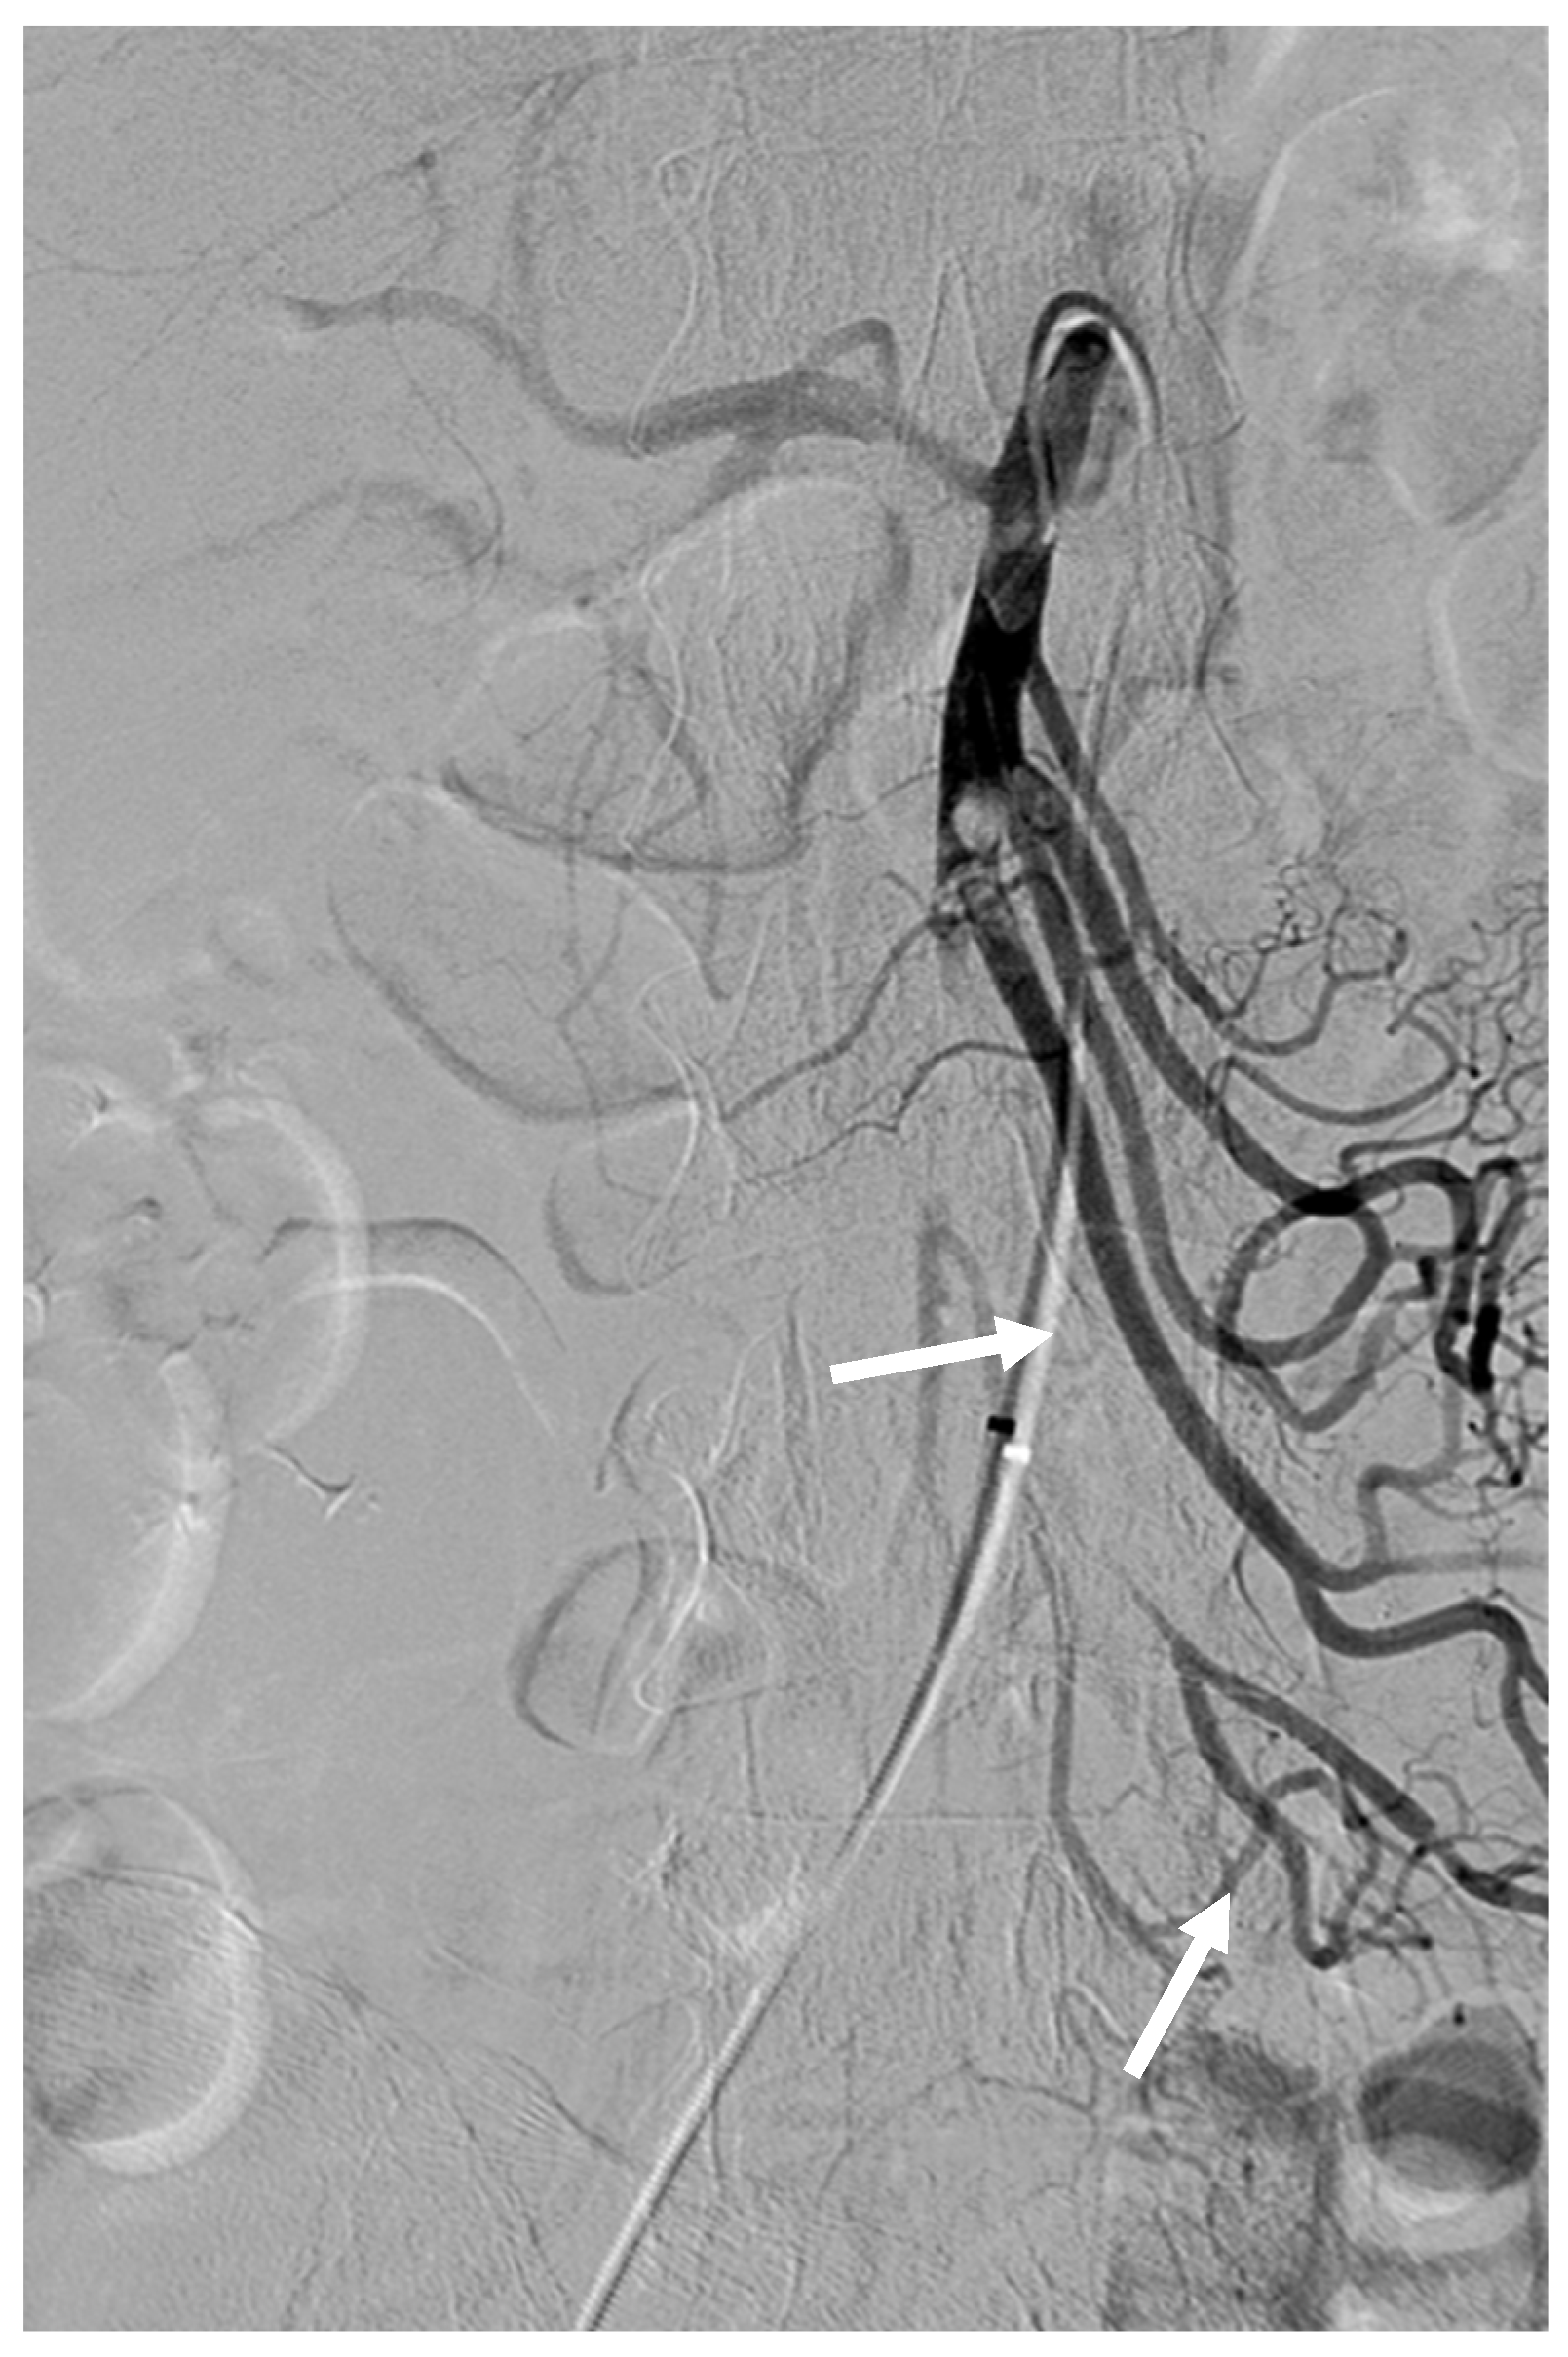

Figure 2. After thrombolysis using 2 mg of rtPA via RH catheter, angiography revealed partial recanalization of jejunal and ileal branches of the SMA (arrows).

After several attempts, we decided to change our plan of performing embolothrombectomy to thrombolysis using a 5 Fr RH catheter and microcatheter (Progreat Lambda, Terumo, Somerset, NJ, USA) with rtPA. We diluted 5 mg of rtPA in 25 mL of saline and 25 mL of contrast solution to prepare an rtPA solution. Subsequently, the SMA was selectively catheterized using a 5 Fr RH catheter. rtPA (2 mg; 20 mL of rtPA solution) was carefully injected (1 mg per 10 min) through the RH catheter. After thrombolysis, angiography revealed partial recanalization of the proximal SMA and its jejunal and ileal branches (Figure 2). Segmental SMA occlusion with sluggish jejunal flow remained, and no visible colic flow was observed.

A 1.9 Fr microcatheter was advanced immediately in front of the SMA occlusion site, and 0.5 mg of rtPA (5 mL solution) was injected for 10 min. After the injection, angiography revealed partial recanalization of right colic flow. The microcatheter was then advanced into the middle and distal branches of the SMA, and rtPA (0.5 mg) was injected again for 10 min. Additionally, the CHA and splenic artery were selectively catheterized using a 5 Fr RH catheter and a microcatheter. Subsequently, 0.5 mg of rtPA was injected into each artery in front of the occluded site. The final angiogram revealed near-complete revascularization of the SMA (Figure 3). To avoid bleeding complications, no additional rtPA was administered.